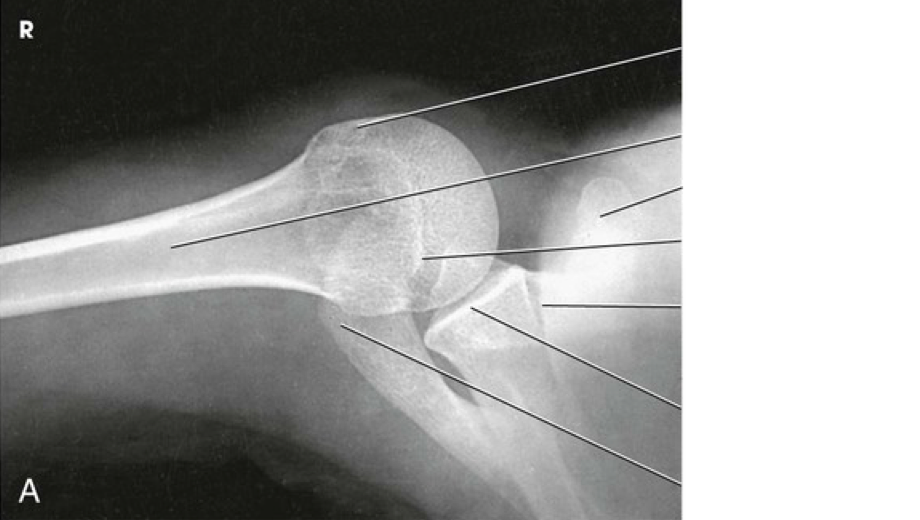

Question 12

Question

Label the image

Image:

c91d01a3-048a-41fe-a502-16f316f7c8ee (image/png)

Answer

lesser tubercle

humerus

coracoid process

acromioclavicular joint

clavicle

scapulohumeral joint

acromion